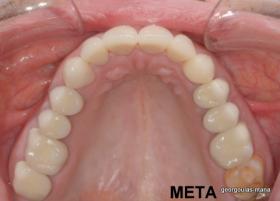

ΟΛΙΚΗ ΑΠΟΚΑΤΑΣΤΑΣΗ ΑΝΩ ΓΝΑΘΟΥ

Η ασθενής ήταν δυσαρεστημένη από την εμφάνιση των άνω δοντιών της. Ήθελε τα δόντια της να αποκτήσουν ομοιόμορφο, πιο λευκό χρώμα κ να αποκτήσει ένα πιο αρμονικό χαμόγελο με φυσική εμφάνιση. Λόγω των εκτεταμένων εμφράξεων σύνθετης ρητίνης στα πρόσθια δόντια, των εμφράξεων αμαλγάματος στα πίσω αριστερά δόντια αλλά και της υπάρχουσας γέφυρας στα πίσω δεξιά δόντια, και σε συνδυασμό με την επιθυμία της ασθενούς για φυσικό αποτέλεσμα αποφασίστηκε η τοποθέτηση ολοκεραμικών στεφανών στα δόντια της άνω γνάθου. Στη θέση του δεύτερου προγομφίου δεξιά τοποθετήθηκε εμφύτευμα. Πραγματοποιήθηκε περιοδοντική θεραπεία, ενδοδοντικές θεραπείες (απονευρώσεις) κ τοποθετήθηκαν ενδορριζικοί άξονες υαλονημάτων όπου κρίθηκε απαραίτητο. Σε όλη τη διάρκεια της θεραπείας η ασθενής ήταν καλυμμένη αισθητικά κ λειτουργικά με προσωρινές αποκαταστάσεις.